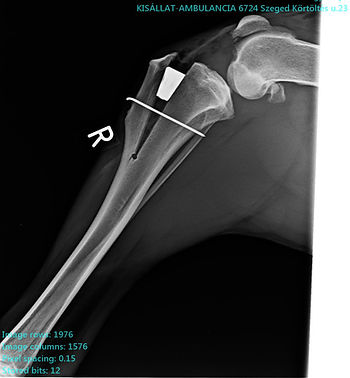

One very effective surgical solution, after cleaning the joint, is to modify the joint angle by inserting a special integrating wedge. This changes the plane of the patellar tendon so that it becomes perpendicular to the tibial plateau. In this way, this tendon—together with the corrected angulation—takes over the function of the original cruciate ligament and bears the load.